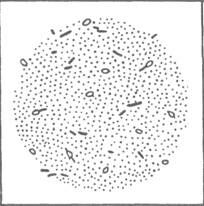

Морфология. Палочка ботулинум — это подвижная крупная палочка, образует споры, расположенные к одному концу клетки, в результате чего микроорганизм принимает форму ракетки (рис. 3).

Этот микроорганизм по Граму красится положительно.

Рис. 3. Палочка ботулинум (CI. Ьоtulinum